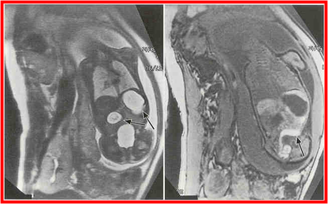

胎儿MRI

多个肠扩张 蜂巢状分布